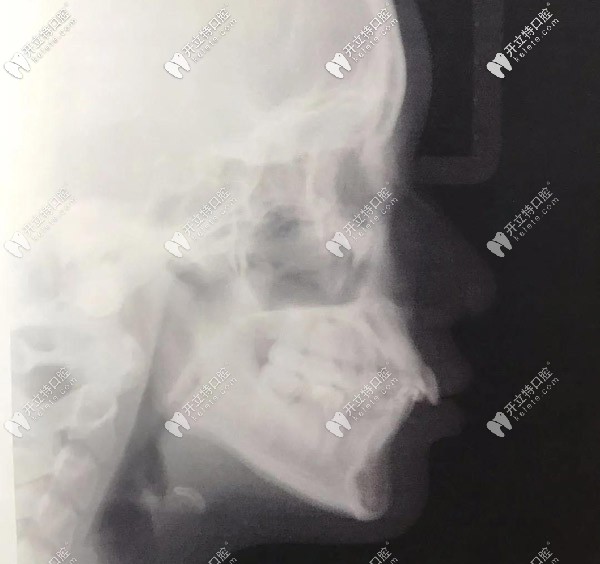

全口X光,牙齒很不齊

▲全口X光,牙齒很不齊